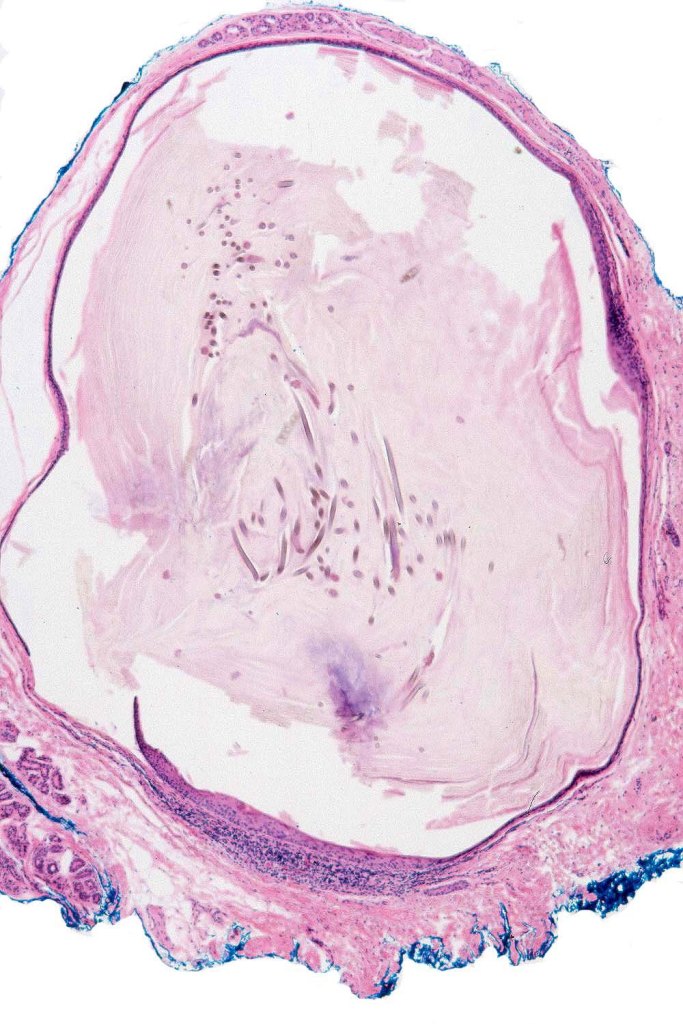

•Mid-dermal thin-walled cyst lined by squamous epithelium often with a granular cell layer

•Contains numerous vellus hair fragments

•Characteristic absence of associated sebaceous glands (compare with steatocystoma multiplex)